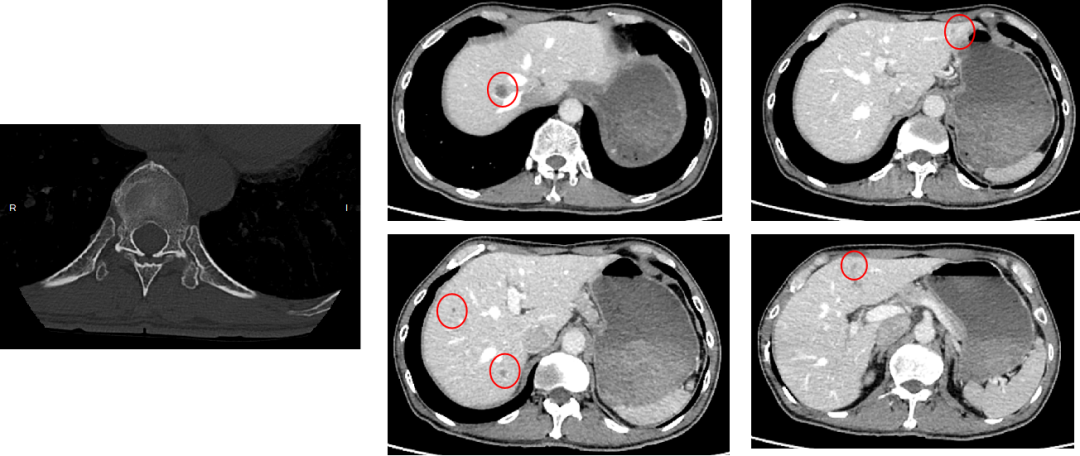

• 影像学:增强CT(2024年7月18日)

image.png

三线治疗(2024年7月起)